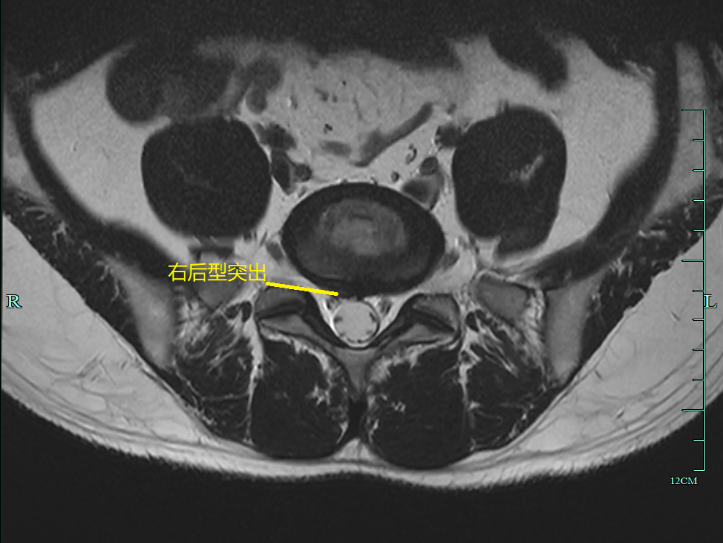

女性,35 岁, L5/S1 椎间盘突出,右后型